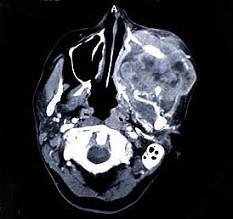

问题 以下关于上颌窦癌(见图)的叙述,哪项是错误的 ( )

选项 A.肿瘤发生部位不同可出现不同临床症状 (如鼻塞、复视、张口受限等) B.早期无症状而不易发觉 C.早期即有明显的骨质破坏 D.远处转移较少见 E.以鳞状细胞癌为最常见

答案 C